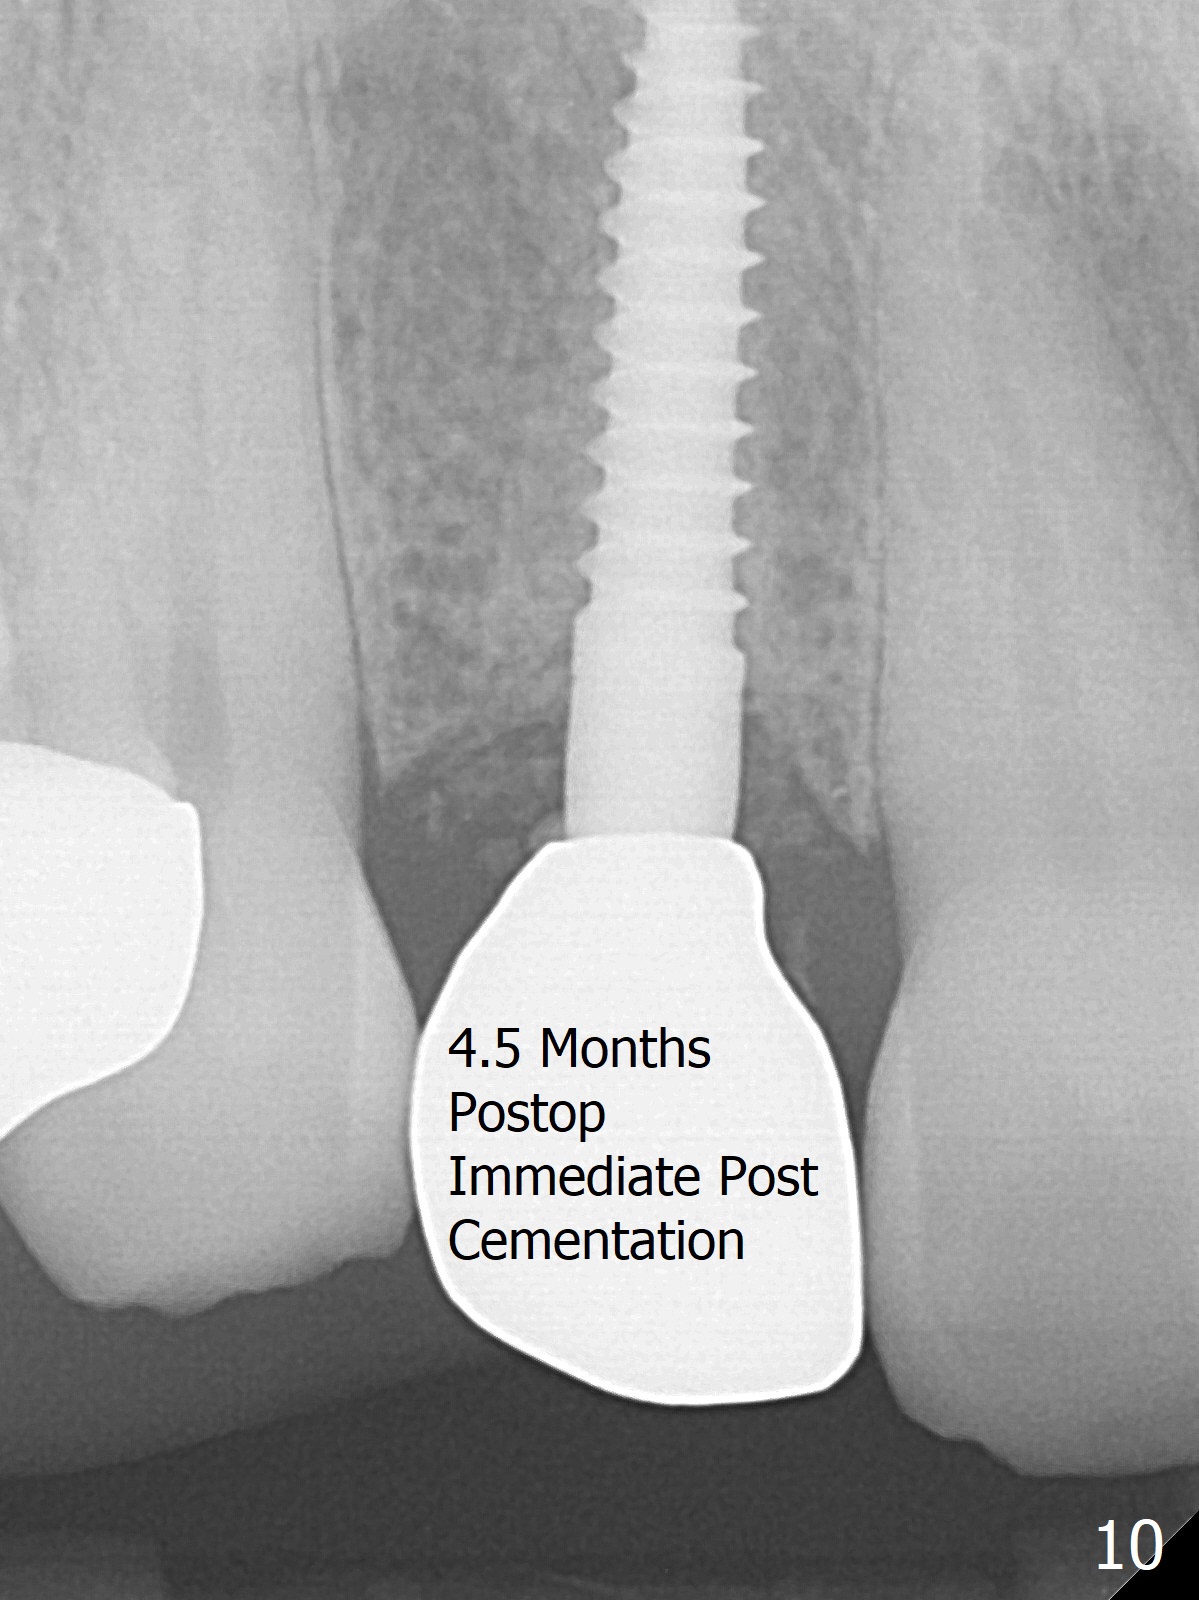

The rebonded crown at #7 debonds in a few days. There is deep anterior overbite and buccal concavity (Fig.1 *). The equigingival fracture (Fig.1,2) seems difficult to restore considering lack of posterior support (lower RPD in Fig.1). Buccal shield is tried in spite of the long root. It is not easy to tell whether the infected apex is removed due to the deep socket. In fact the apical buccal plate perforates because of use of surgical handpiece. Finally the buccal shied is removed. PA confirms the retained apex (Fig.3 *). The initial osteotomy with 1.5 mm drill in place is off trajectory (Fig.4). After adjustment of the trajectory of osteotomy (Fig.5), a 3x16(2) mm 1-piece implant is placed within normal limit (10-15 Ncm, Fig.6)). In fact bone graft is placed before (Fig.6,7 arrowhead; to repair apical buccal plate perforation) and after (Fig.6 *) implantation. The gingiva (including papillae) remains normal around the provisional 3 months postop (Fig.8). The bone graft becomes more organized 3 months postop (Fig.9), continues to do so 4.5 months postop (Fig.10) and becomes dense coronally 9 months post cementation (Fig.11: *).